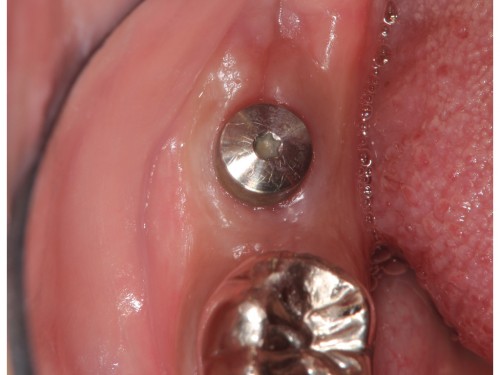

想定していた位置にインプラント治療ができました。

インプラント治療を行ったのち仮歯を作ります。

仮歯でしばらく噛み心地を確認してもらった後、セラミックの歯に置き換えていきます。